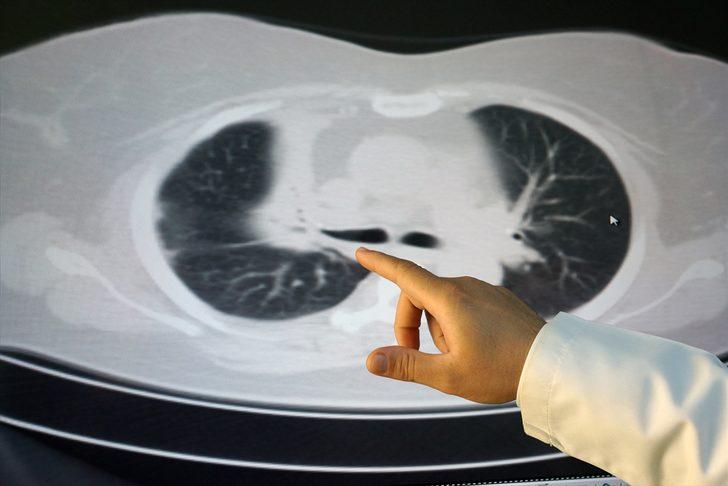

Doktorların uyguladığı tüm tedavilere rağmen Akkuş bir türlü sağlığına kavuşamadı. Yapılan tetkiklerde akciğerde büyük bir kitle tespit edildi. Akkuş'a yapılan iki kez biyopsi de temiz çıkarken doktorlar, kitlenin kanserli olabileceği şüphesiyle Akkuş'u ameliyata aldı.

Doç. Dr. Kenan Can Ceylan'ın gerçekleştirdiği ameliyatta, akciğerde bulunan çeşitli ebatlardaki ceviz parçalarının damarları tıkadığı tespit edildi.Ceviz parçalarının çıkarılması sonrasında Akkuş sağlığına kavuştu.

Doç. Dr. Ceylan ise hastanın kendilerine akciğer kanseri şüphesiyle geldiğini, ameliyatta çok şaşırdıklarını ifade etti. Ceylan, "Hastanın, yıllar önce yuttuğu ceviz parçalarına bağlı sağ üst akciğerinin tamamen tıkandığını, burada biriken balgamların akciğeri tamamen harap ettiğini fark ettik.